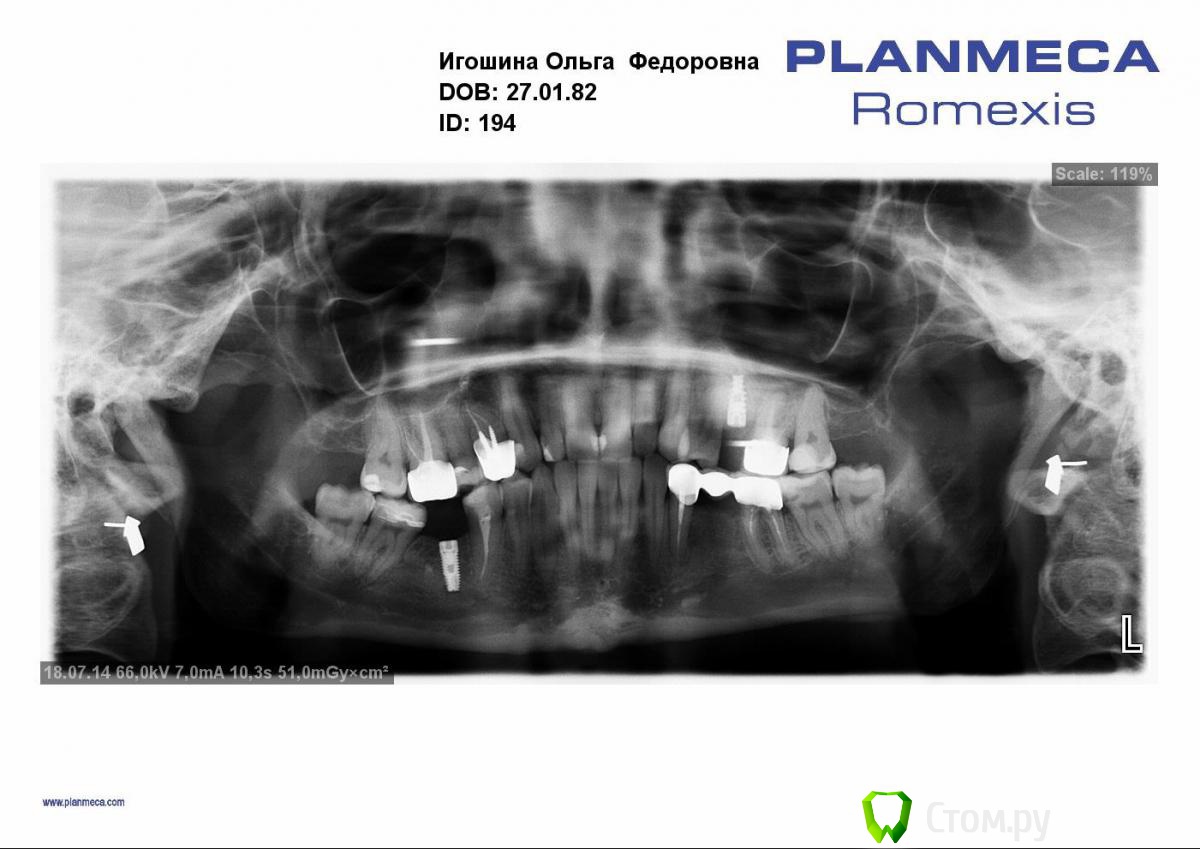

Тимур86 Опубликовано 18 июля, 2014 Поделиться Опубликовано 18 июля, 2014 В подбородочной области?или мне кажется? Ссылка на комментарий

АнтонТЛТ Опубликовано 18 июля, 2014 Поделиться Опубликовано 18 июля, 2014 Имеется ввиду темное пятно или светлое? Ссылка на комментарий

Тимур86 Опубликовано 18 июля, 2014 Автор Поделиться Опубликовано 18 июля, 2014 Размытое светлое пятно!темное только что увидел) Ссылка на комментарий

АнтонТЛТ Опубликовано 18 июля, 2014 Поделиться Опубликовано 18 июля, 2014 (изменено) Светлое это подбородок))) Вероятно сильно выражен и поэтому толстый массив кортикалки в вестибуло-лингвальном направлении создает участок радиоопаковости Изменено 18 июля, 2014 пользователем АнтонТЛТ 3 Ссылка на комментарий

4ebstom Опубликовано 20 июля, 2014 Поделиться Опубликовано 20 июля, 2014 Апекальнее 31 зуба-выходит сосуд или мерещится? Ссылка на комментарий

sergio Опубликовано 20 июля, 2014 Поделиться Опубликовано 20 июля, 2014 В подбородочной области?или мне кажется?Ничего особенного там нет Ссылка на комментарий